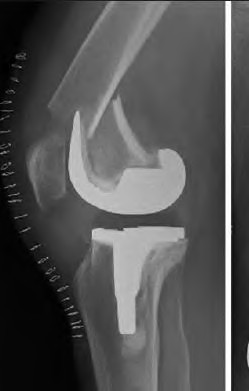

A 65-year-old woman with painful knee arthritis and the deformity seen in Figure A, is scheduled to undergo a total knee arthroplasty. All the following are risk factors for a post-operative peroneal palsy EXCEPT:

Figure A demonstrates and AP radiograph of the knee showing end-stage arthritis with severe lateral compartment narrowing.